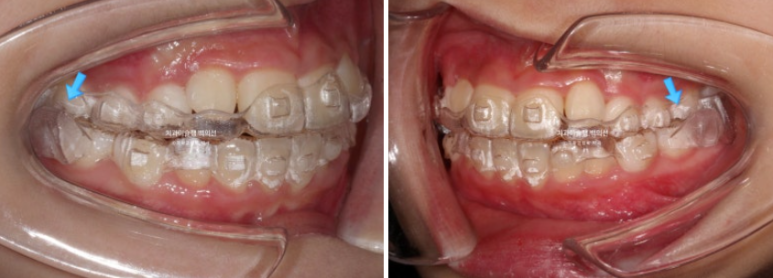

24.12

파란화살표 부분을 보자면

장치 양옆에 날개처럼 튀어나온 부분이 Wing 이며 이 부분이 아래턱의 위치를 정상위로 유도합니다.

23.11

사진의 파란화살표처럼 위 아래 윙 끼리 엇갈려 물리며 아래턱을 전방위치 시키며, 최대성장기와 맞물리면 하악골 성장까지 유도하게 됩니다.

23년 11월 24년 7월까지 53번 마지막 장치까지 다 끼면서 MA 단계를 마쳤습니다.